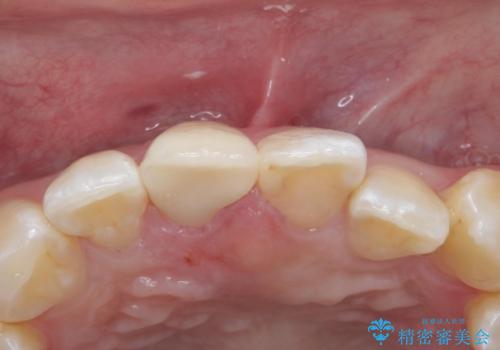

色・形ともに改善され、大変喜んでいただけました。

- 右上1: 仮歯/11,000円、ジルコニアクラウン(スタンダード)/121,000円 合計132,000円(税込)費用は治療当時の料金となります